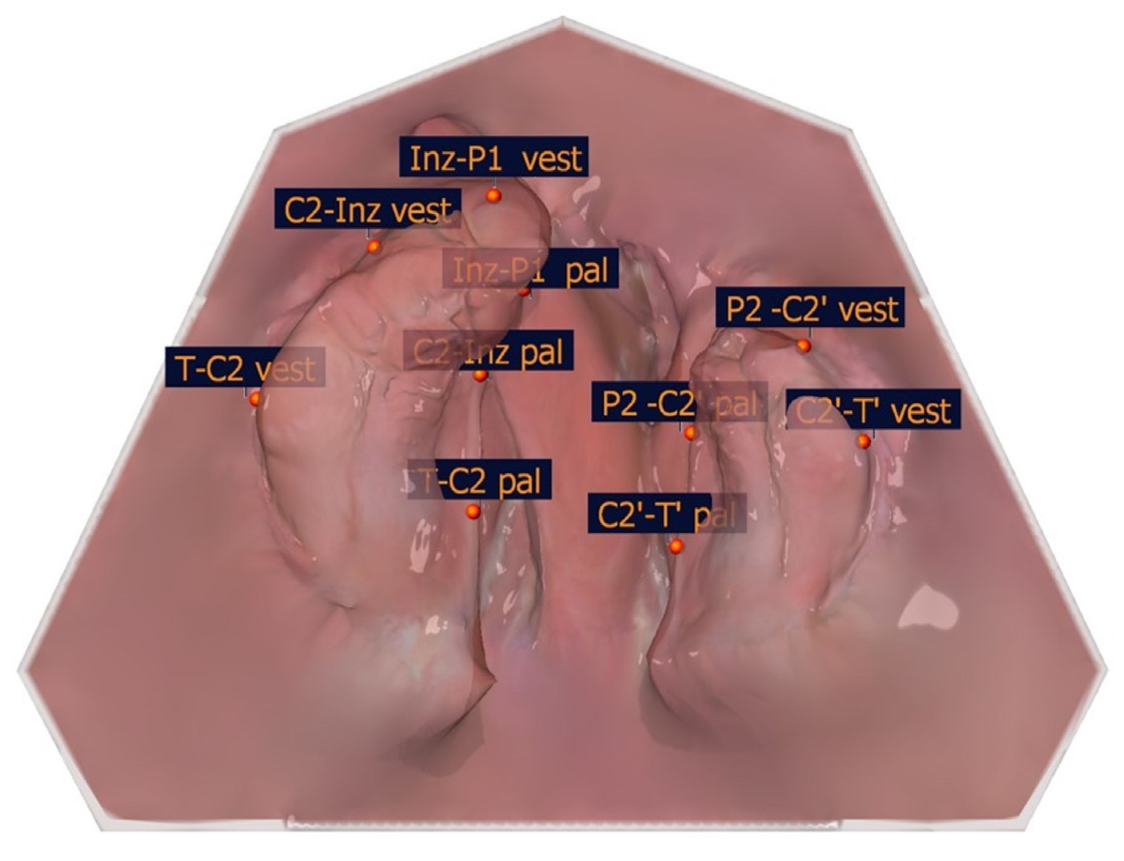

The large and small segments were divided into subsegments to identify the transversal landmarks (T-C2, C2-Inz, and Inz-P1 for the large segment and P2-C2′ and C2′-T′for the small segment). The most vestibular and most palatal points in each section were determined. For the segmental width measurements, the greatest distance perpendicular to the length measuring sections of the partial jaw segments defines the greatest width of the jaw segments. The segment width measurements are shown in Table 4, and an exemplar is shown in Figure 9.

Figure 9. Exemplary illustration of the segment width measurements.